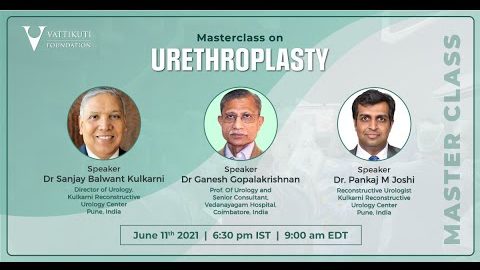

Master Class On Urethroplasty

Masterclass, Urology ';